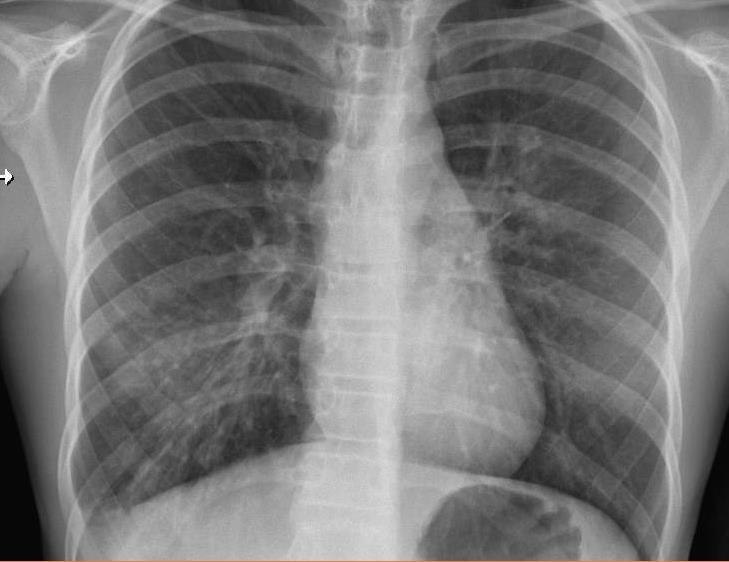

Imaging of Covid 19 infection in children COVID 19 Late

Late

37